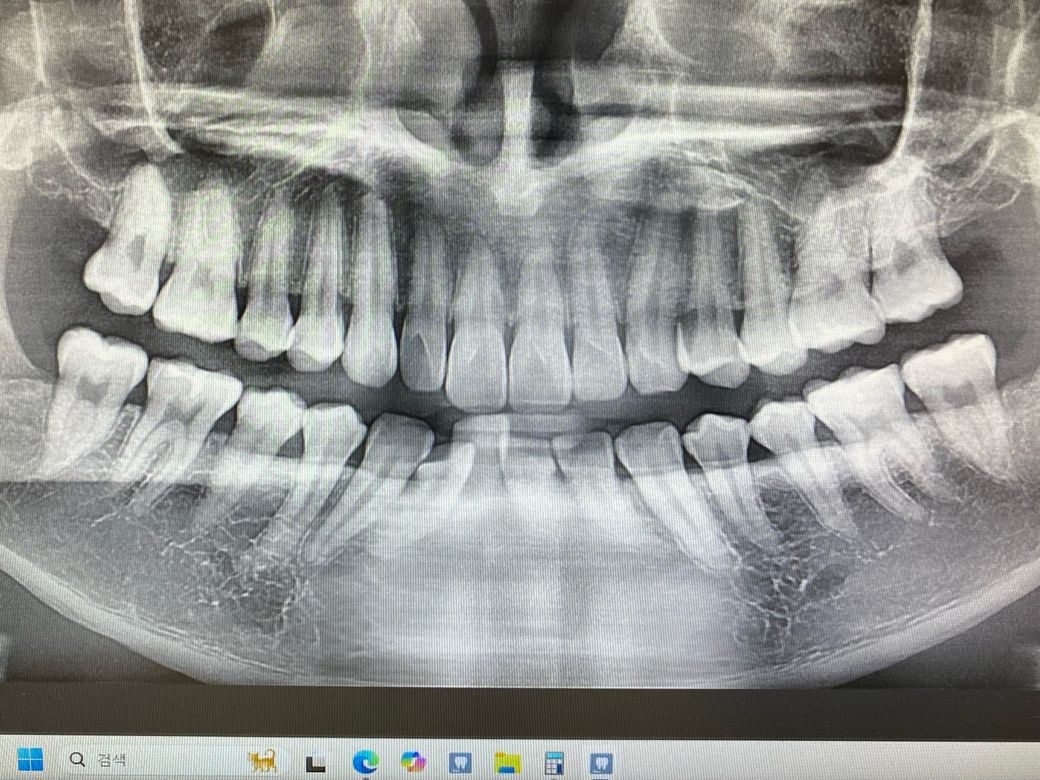

1번 치과는 왼쪽 위 4번째 안쪽면에 인접면 충치

왼쪽 위 2번째 어금니 레진속 2차 충치로

2번 치과는 치료 할 수준이 아니다 경과를 지켜보자

3번 치과도 이런건 치료 안한다 경과를 지켜보자

1번과 2, 3번의 진료가 너무 상반되어 질문드립니다

육안상으로보면 치아 사이에 충치가 잇는거 같습니다. 관리를 잘하시면 진행이 안되겟지만 관리가 안되면 충치 진행이 빨라져서 신경치료를 해야될수도 잇으니 저라면 미리 치료를 하라고 권유할것같습니다 .

육안으로 봤을 경우에는 인접면에 충치가 있는 것으로 보이긴 합니다. 하지만 엑스레이 사진상으로 크게 보이지 않기 때문에 관리를 해서 사용할 수 있는 경우도 있습니다. 충치가 더 커지는 것을 방지하기 위해 예방적으로 치료를 하고자 한다면 치료가 필요할 수 있으며 그렇지 않다면 관리를 하면서 상태를 지켜볼 수 있습니다.